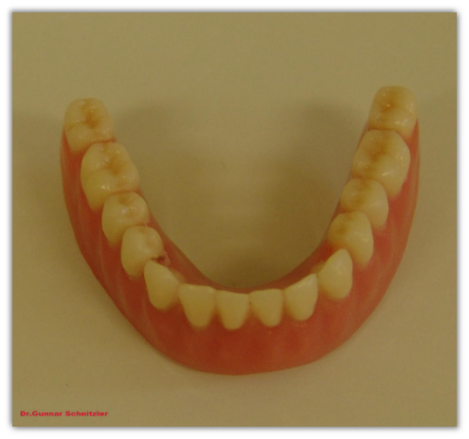

Die fertige Prothese im Unterkiefer in der Draufsicht.